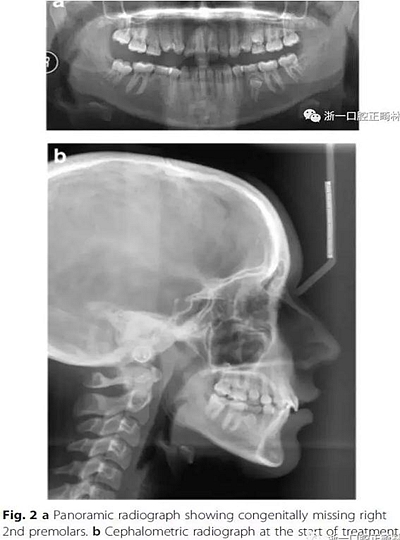

影像學檢查,右側(cè)第二前磨牙和所有第三磨牙先天性缺失;

頭側(cè)分析,骨性I類關(guān)系,高角型